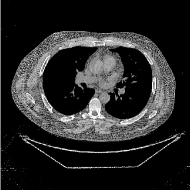

This section compares the reconstruction quality and runtime among the proposed MBIR method, PWLS-ST-, and other three MBIR methods, PWLS-EP, PWLS-DL, and PWLS-ST-. Table I shows that, for both 2D and 3D sparse-view CT reconstructions of the XCAT phantom, the proposed PWLS-ST- model outperforms PWLS-EP and PWLS-ST- in terms of RMSE. In addition, PWLS-ST- using a square transform (of size ) achieves lower RMSE than PWLS-DL using an overcomplete dictionary (of size ) for 2D sparse-view reconstructions. Fig. 3(a) and Fig. 4 show the reconstructed images for 2D and 3D phantom experiments, with different reconstruction models and different number of views. (See the corresponding error maps in the supplement.) The proposed PWLS-ST- consistently gives more accurate image reconstructions compared to other MBIR methods. Specifically, PWLS-ST- has smaller errors in the heart region (see zoom-ins in Fig. 3(a)) of 2D reconstructions than PWLS-DL and PWLS-ST-. In addition, compared to PWLS-ST-, PWLS-DL and PWLS-ST- have some ringing artifacts around the edges with high transition, e.g., edges between air and soft tissues. (See a comparison of profiles of PWLS-ST- and PWLS-ST- in the supplement.) In particular, PWLS-ST- and PWLS-DL give more visible ringing artifacts for 2D reconstruction from fewer views, and PWLS-ST- has these ringing artifacts for 3D reconstructions regardless of the number of views (see zoom-ins in Fig. 4). Table II reports runtimes of different MBIR methods in reconstructing the -views XCAT phantom scan. (FBPConvNet is a non-MBIR method and its runtime for processing a image is approximately one second with a TITAN Xp GPU.) While providing better reconstruction quality, the proposed Algorithm 1 of PWLS-ST- has shorter runtime compared to the algorithms of PWLS-DL and PWLS-ST- in Section III-A. Similar to the PWLS-EP algorithm, the reconstruction time of the PWLS-DL, PWLS-ST-, and PWLS-ST- algorithms can be further reduced by using ordered subsets [51].

Fig. 3(b) shows that when tested on the clinical scan data, the proposed PWLS-ST- method improves reconstruction quality in terms of noise and artifacts removal (e.g., see zoom-ins for soft-issue regions), and edge preservation (e.g., see zoom-ins for bone regions), compared to PWLS-EP and PWLS-ST-. Compared to PWLS-DL, PWLS-ST- achieves comparable image quality, but requires less computational complexity.

![]() |

| (a) 2D fan-beam CT experiments |

| (b) 3D axial cone-beam CT experiments |